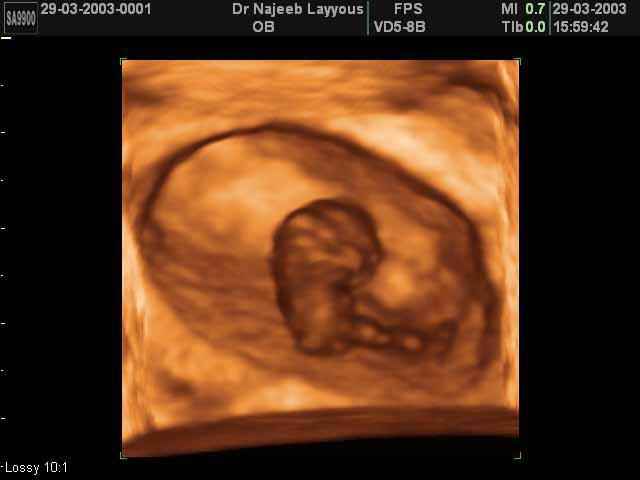

3D First Trimester Ultrasound Scan Photos ( Early Pregnancy Ultrasound Photos ) | Dr N Layyous

3D First Trimester Ultrasound Scan Photos